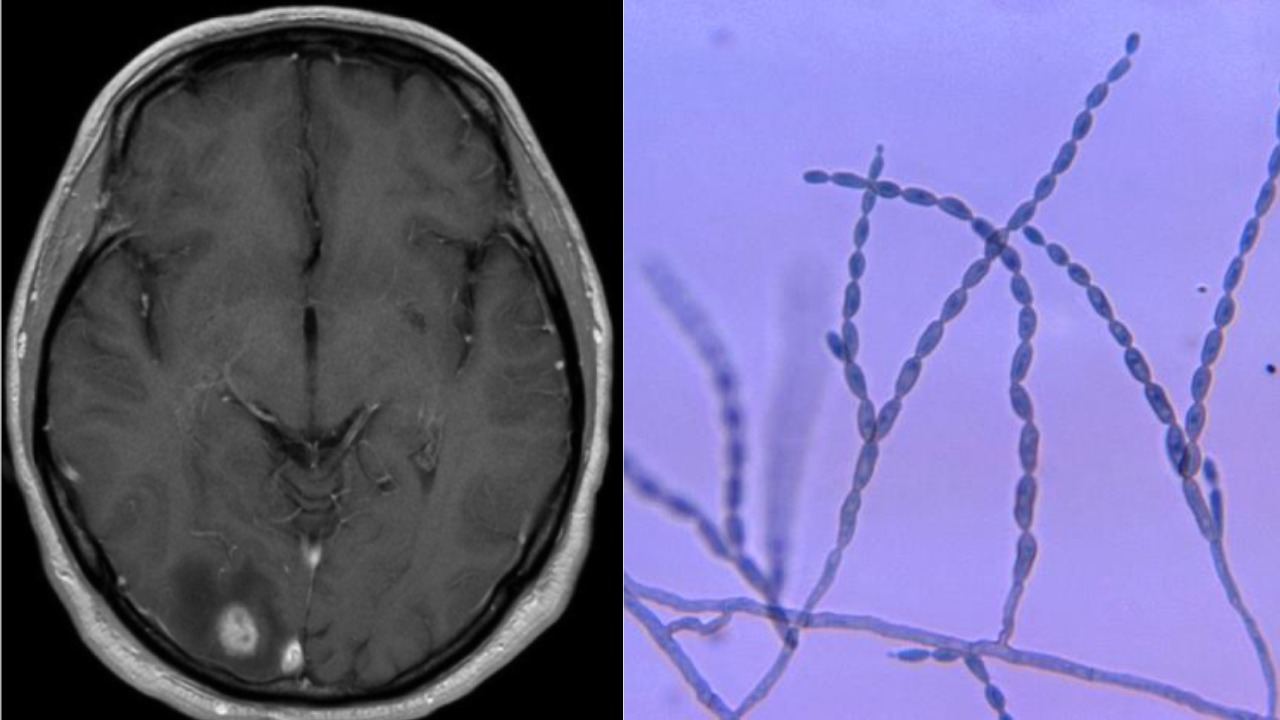

Osem mesiacov po prvých príznakoch bol prijatý do Massachusetts General Hospital v Bostone, kde neurochirurgička zbadala tmavú hmotu. Texaské laboratórium potvrdilo, že Bottenus má extrémne vzácnu tropickú hubu.

Žiaľ, léziu s hubou nebolo možné chirurgicky odstrániť, pretože bola hlboko v mozgu, v citlivých a dôležitých častiach. Lekári preto začali liečbu kombináciou protiplesňových liekov a steroidov, ktoré mali kontrolovať opuch v mozgu.